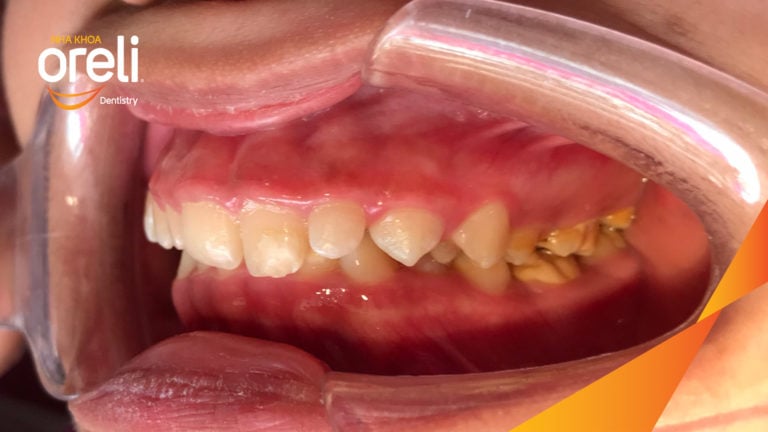

Ca niềng chỉnh cắn sâu nặng kèm cắn chéo vùng răng sau kết quả thực tế tại nha khoa Oreli Niềng răngCắn sâu Xem thêm